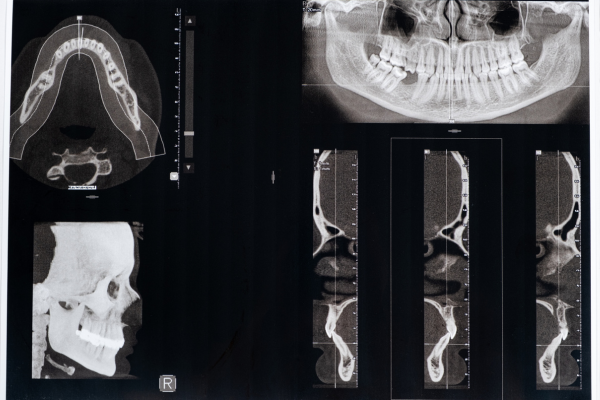

中部ろうさい病院の歯科口腔外科では、インプラント治療を専門的に実施しています。歯を失ってしまった場合、そのまま放置すると咀嚼機能が低下し、食事や発音に影響を及ぼすだけでなく、顎の骨が痩せてしまうリスクも高まります。従来のブリッジや入れ歯に代わる治療法として、インプラントは人工歯根を顎骨に埋入し、その上に人工歯を装着することで、自然な噛み心地と審美性を取り戻すことができます。

中部ろうさい病院では、骨移植による顎堤造成や高度顎堤吸収患者への対応も可能であり、長期的な予後を考慮した治療計画を立案しています。また、埋入手術の際には、全身麻酔や静脈内鎮静法を適用することで、患者様の負担を軽減し、安全性を高めています。特に、痛みに対する不安がある方には、眠たくなる薬を使ったリラックスした状態での治療も可能です。

顎変形症は、上下の顎の骨格にずれや不調和があることで、噛みにくさや発音のしづらさに加え、見た目のバランスにも影響を与える疾患です。症状によっては顎関節に負担がかかり、日常生活に支障をきたすこともあるため、専門的な診断と治療が欠かせません。

矯正治療の一環として、歯が並ぶスペースが不足している場合は抜歯が必要になることがあり、複数の歯や埋伏歯を短期入院で安全に処置することも可能です。また、インプラントアンカーを活用することで、固定源を確保しながら効率的で精密な歯の移動を行うことができ、より理想的な矯正治療を実現できます。

重度の顎変形症では、矯正治療と併用して顎矯正手術を行い、顎骨を適切な位置に移動させることで噛み合わせと顔貌を改善します。さらに、歯を失っている場合にはインプラント治療を組み合わせ、咀嚼機能の回復と自然な見た目の両立を目指します。

埋伏歯抜歯:難症例にも対応する専門技術

中部ろうさい病院の歯科口腔外科では、親知らずを含む埋伏歯の抜歯を専門的に行っています。埋伏歯とは、正常に生えずに顎骨内に埋まってしまった歯のことで、特に親知らずに多く見られる症状です。埋伏歯が放置されると、隣接する歯に圧力がかかり、歯列不正や虫歯、歯周病の原因となるほか、炎症が広がることで顔の腫れや開口障害を引き起こすことがあります。

中部ろうさい病院では、難症例や複数の埋伏歯の抜歯も対応可能です。痛みや不安を軽減するため、静脈内鎮静法を活用してリラックスした状態での手術を実現しており、必要に応じて全身麻酔を導入することで、安全で確実な抜歯を行っています。手術後には、出血や腫れを最小限に抑えるためのケア方法を指導し、術後の合併症にも細やかに対応しています。